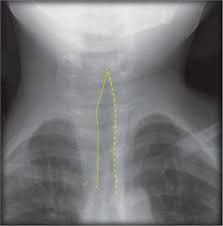

A pesar de lo alarmante que puede resultar el sonido de la tos, el diagnóstico es fundamentalmente clínico. En la mayoría de las situaciones típicas no es necesario realizar análisis de sangre ni radiografías. Solo en casos de duda diagnóstica se recurre a una imagen de cuello, donde se puede observar el llamado signo de la aguja o del campanario, que muestra gráficamente el estrechamiento de la tráquea en forma de V invertida.